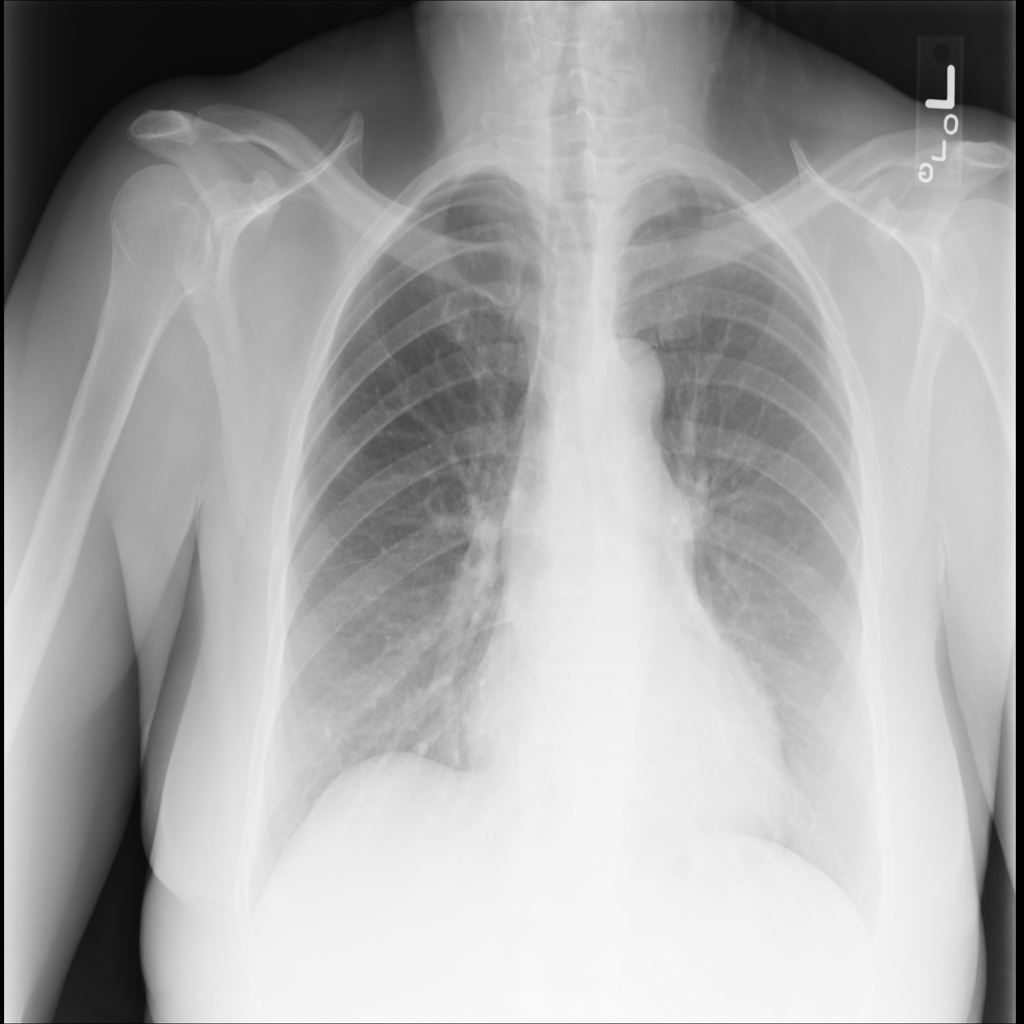

PAT-3384 · IMG-000Cardiomegaly

PAT-3384 · IMG-000

AP